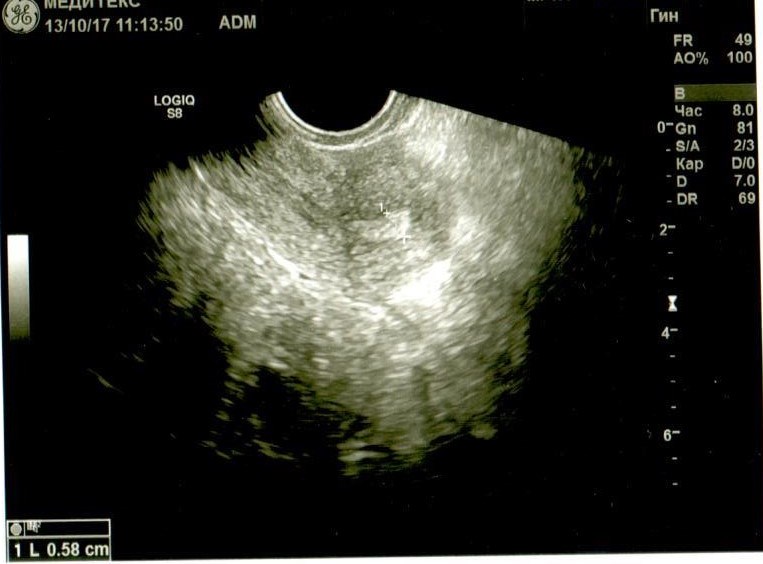

Если можно, посмотрите. Буду очень благодарна. Не очень в этом разбираюсь, поэтому выкладываю все снимки и заключение узистки.

Добрый день! У Вас в самой структуре яичника имеются гиперэхогенные включения, которые говорят о перенесенном воспалении, при этом о спайках может говорить только расположение яичников возле матки ( это если опираться на описание, так как на фото не видно). Однозначно, имеет место хронический оофорит. И в эндометрии мне не нравится зона в области дна. Врач ее даже выделила, но не описала. Эндометрий неоднородный, стоит сделать УЗИ на 5 день цикла повторно.